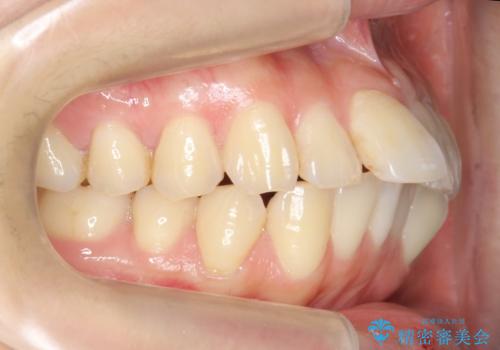

出っ歯・過蓋咬合 奥歯を後ろに下げて非抜歯で治療

- 出っ歯を主訴に来院。

下の前歯が上の前歯の根元に当たっている過蓋咬合でした。

また、右のかみ合わせだけ小臼歯1本分、上が前にずれてしまっていました。

ずれの程度は大きかったので抜歯も考えられましたが、患者様と相談し、治療期間はかかりますがマイクロインプラントを使用して非抜歯で治療を行うこととしました。

難しい場合は抜歯もあり得ると説明しましたが、結果非抜歯で右のかみ合わせをよくできました。

また、過蓋咬合のため、下の前歯に装置をつけるのが大変難しかったですが、しっかり治療しました。